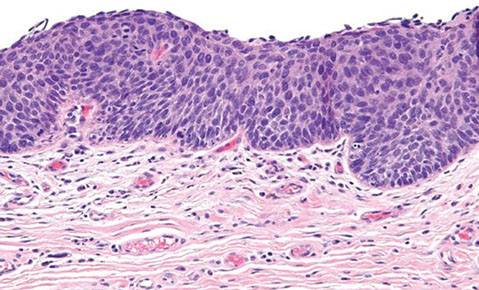

Lichen sclerosus

aka lichen sclerosus et atrophicus

chronic disease with lots of lymphs, usually in post-menopause which itches a lot

- MC in post-menopausal women, may be 2/2 autoimmune dz

Gross: atrophic, thin skin (cigarette paper) with white-red patches

Micro: Marked thinning of epidermis c basal cell degeneration, hyperkeratosis (excessive keratinization), loss of rete pegs, vacuolar interface rxn pattern c dermal sclerosis bwt chronic inflam and epithelium / vessel walls

Tx: best if caught early; topical roids, then oral roids

- should bx to r/o malignancy, may turn to SCC (1/5 get SCC after 4 yrs)

Px: in rare cases assoc c carcinoma, there is p53 overexpression